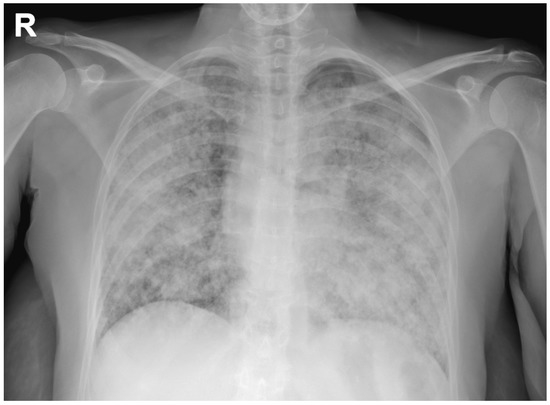

A chest radiograph showed diffuse, alveolar and interstitial lung involvement with micronodules tending to coalescence (Figure 1). This radiographic pattern, known as “galaxy sign”, consistent with diffuse, coalescing nodular miliary pulmonary involvement, simulating a mass-like region or a non-specific alveolar opacification of the lungs [1].

Figure 1. Chest radiograph showing a diffuse, alveolar and interstitial lung involvement with coalescing micronodules, simulating a non-specific alveolar opacification of the lungs (galaxy sign) (R: right side).